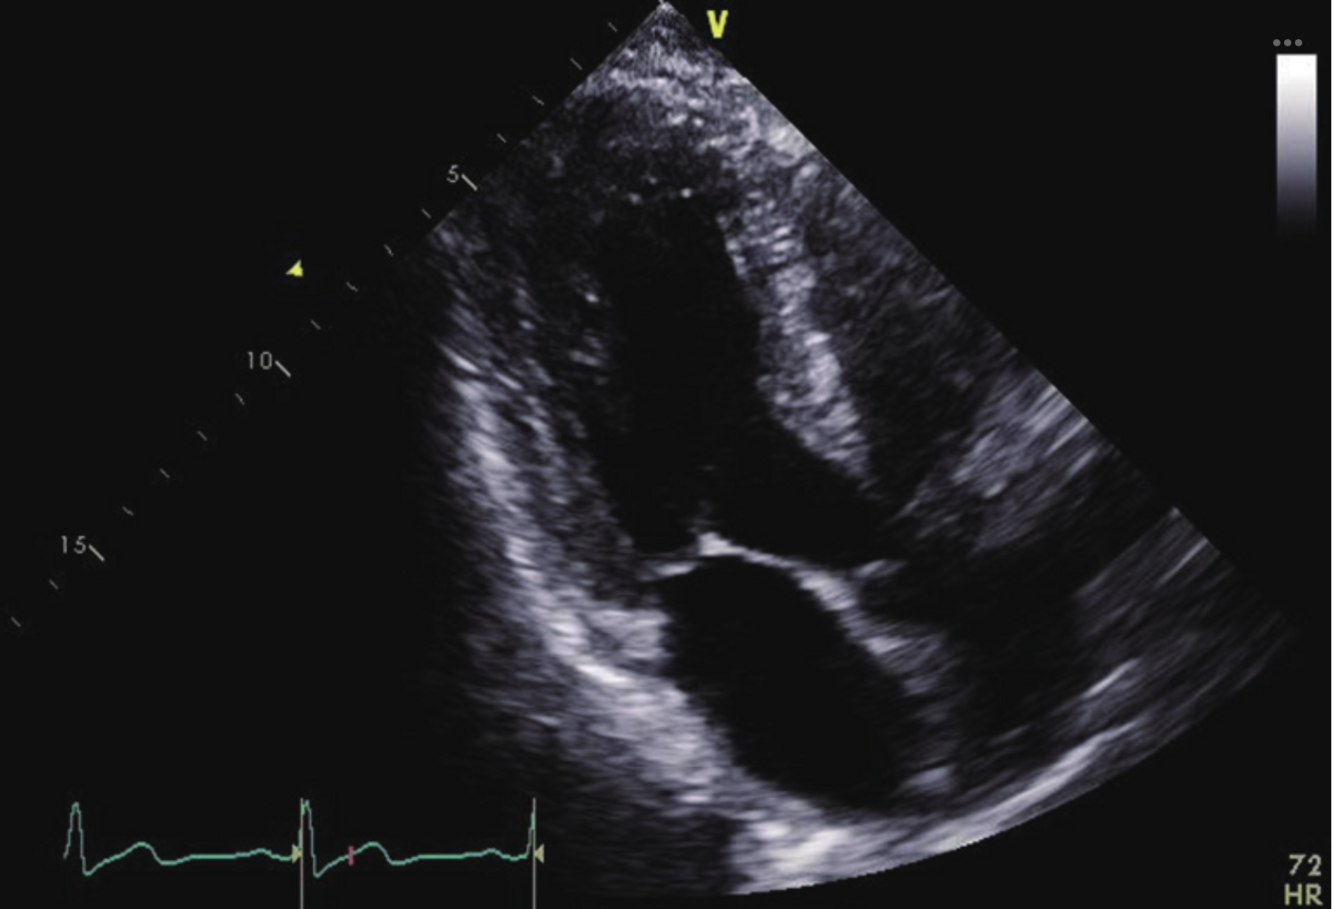

Q

What vessel is being sampled in this image? Be specific.

A

Descending Aorta